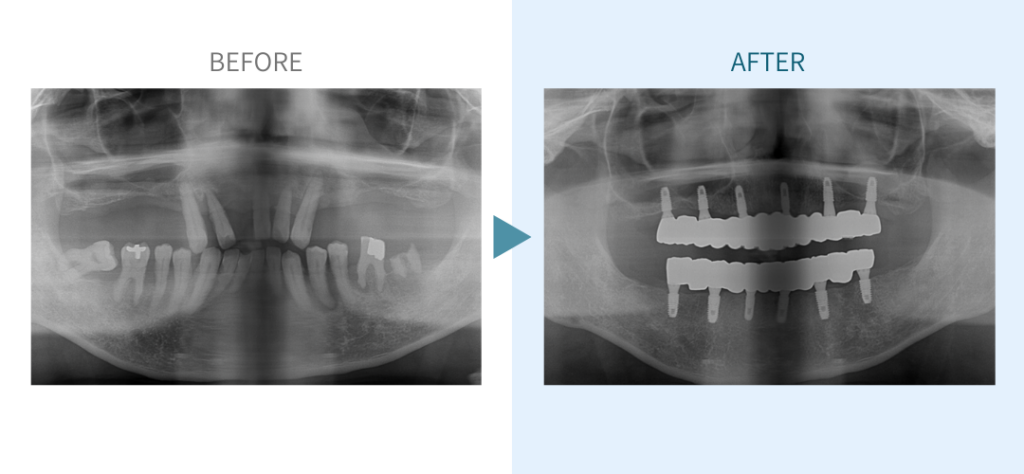

デンタルチームジャパンでは、サイナスリフト(上顎洞底挙上術)や骨造成など、他院で「骨が足りない」と断られた難症例にも対応しています。

私たちは、難症例に関する治療法を学会でも発表しており、その豊富な実績と技術力が評価され、全国から患者様が来院いただいております。

こちらではその一部の症例についてご紹介します。